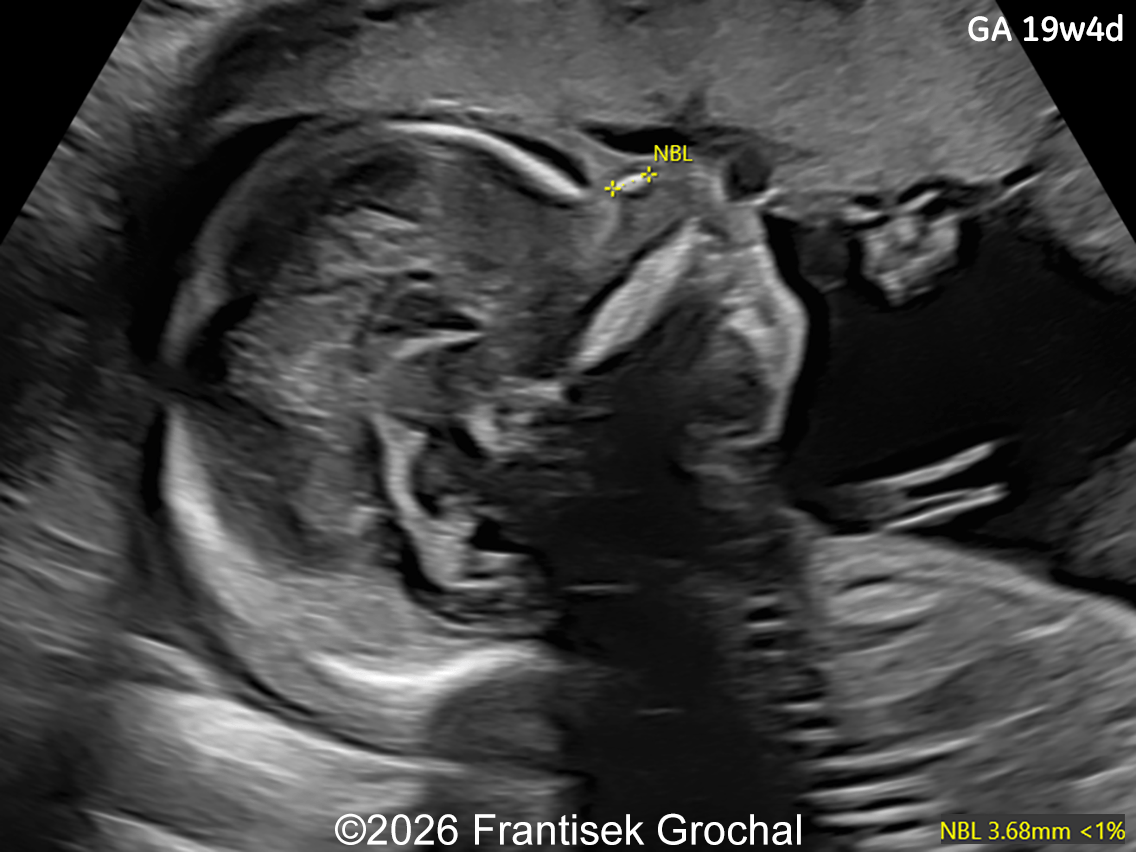

Image 2

• Right-sided microphthalmia

19+4 weeks of gestation; transverse view through the fetal orbits demonstrating right-sided microphthalmia.

Image 2 19+4 weeks of gestation; transverse view through the fetal orbits demonstrating right-sided microphthalmia.